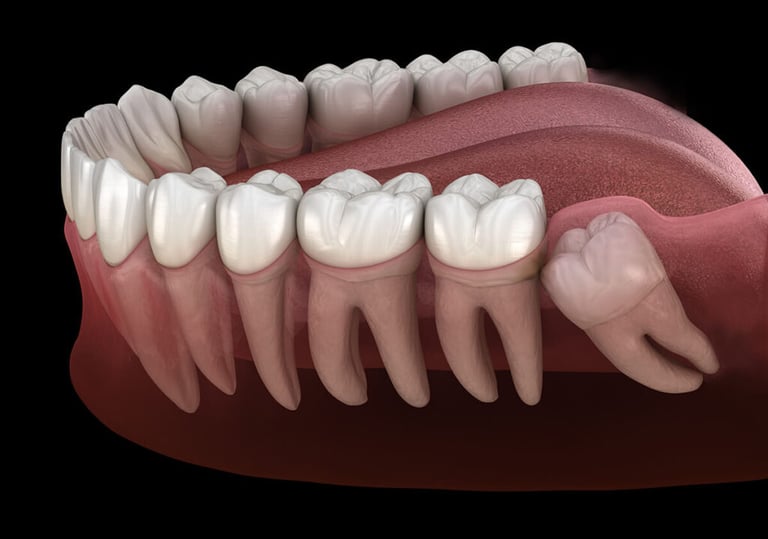

3. Everyone Will Need All Four Wisdom Teeth Removed

If they cause pain and become impacted even if they don’t come up through the gums; sometimes they can grow in sideways and hit the roots of the neighboring molars or shift things around in the jawbone itself. In cases like this, they would still need to be removed, even if they aren’t visible.

4. All Four Must Come in Before They Can Be Removed

Some people think that you need to wait for all four wisdom teeth to grow in before you can get them removed. As we mentioned earlier, not everyone will grow four wisdom teeth, and not all of them even need to be removed. There are many people who only need to have one or two taken out, or who have their teeth removed in multiple procedures